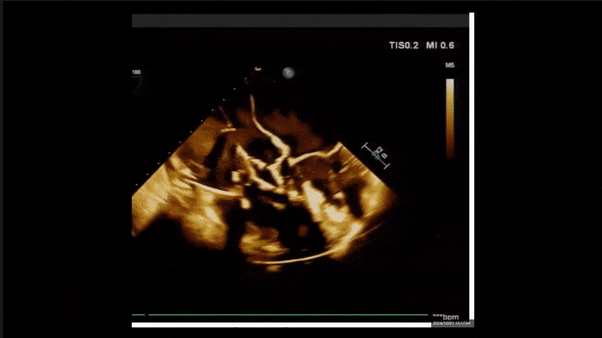

術(shù)后即刻返流

術(shù)后即刻返流三維

術(shù)后即刻經(jīng)食道超聲可見(jiàn),三尖瓣假體瓣膜位置合適,牛心包瓣葉運(yùn)動(dòng)狀態(tài)良好,開(kāi)閉正常,瓣周及瓣葉對(duì)合緣處未見(jiàn)明顯返流,心電圖及心包狀態(tài)較術(shù)前無(wú)明顯變化。